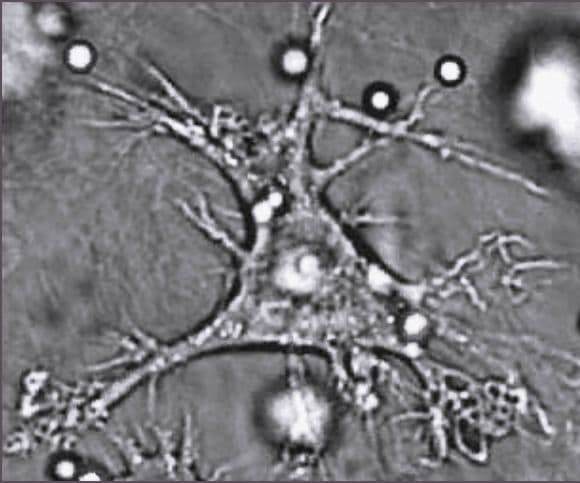

Sel dendritik (bahasa Inggris: dendritic cell, DCcode: en is deprecated ) adalah monosit yang terdiferensiasi oleh stimulasi GM-CSF dan IL-4,[1] dan menjadi bagian sistem kekebalan mamalia.

Bentuk sel dendritik menyerupai bagian dendrit pada neuron, tetapi sel dendritik tidak bekerja pada sistem saraf, melainkan berperan sebagai penghubung sistem imun bawaan dan sistem imun adaptif.

Sel dendritik pertama kali ditemukan oleh Ralph M. Steinman, Dinah S. Lustig, dan Zanvil A. Cohn pada 1972.[2] Saat itu ditemukan sejumlah sel pada organ limpa yang diperkirakan berasal dari sel prekursor pada sumsum tulang atau bagian dari limpa yang disebut pulpa merah.[4] Sel yang ditemukan dapat melekat pada permukaan gelas dan plastik, dan disebut dendritik karena mempunyai fitur morfologis fantastis berupa kemampuan untuk menampilkan berbagai proses seluler dari beragam ukuran dan bentuk.[4] Pada percobaan in vitro lebih lanjut, sel dendritik tidak menunjukkan sifat dan fungsi seperti limfosit, makrofaga atau sel retikular non-fagositik.